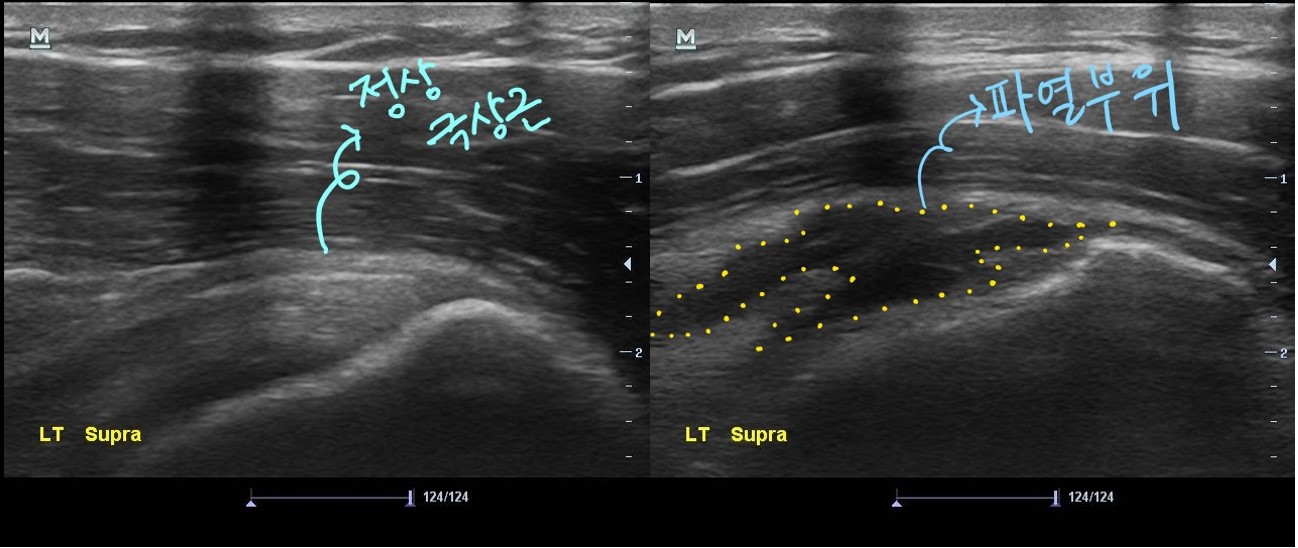

초음파 검사상에서 회전근개 중 하나인 극상근의 파열 정도가 생각보다 심해 보였습니다.

나 : 어깨 힘줄 하나가 상당히 많이 그리고 넓게 파열되어 있습니다.

나 : 초음파 검사상 이정도면 MRI 촬영하고 수술도 고려해봐야 할 상태인데요..

나 : 일반적으로 초음파에서 이정도 파열 소견을 보이면 수술이 필요한 경우가 많습니다